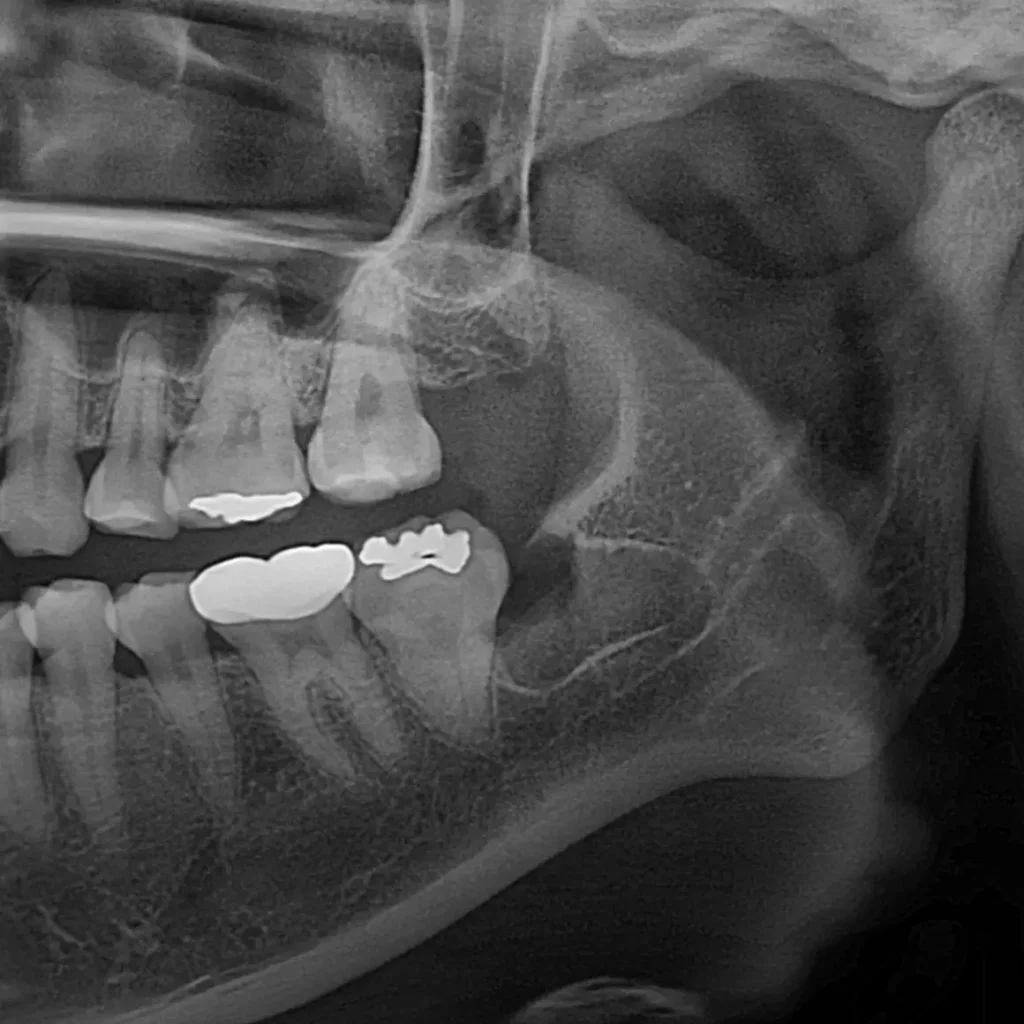

환자분께서는 왼쪽 아래 사랑니 부위가 붓고 통증이 심해 내원하셨습니다.

아픈 사랑니 (왼쪽 아래)

안 아픈 사랑니 (오른쪽 아래)

반대편에는 당장 아프지 않은 매복 사랑니가 있었습니다. 하지만 아프지 않다고 방치하면 다음과 같은 문제가 생길 수 있습니다.

- 사랑니 발치: 왼쪽, 오른쪽 매복 사랑니를 동시에 발치했습니다.

- 충치 치료: 검진 중 발견된 왼쪽 아래 큰 어금니(#36번 치아)의 골드 인레이 하방 충치를 발견하여, 발치와 동시에 크라운 프렙(다듬기)까지 완료했습니다.